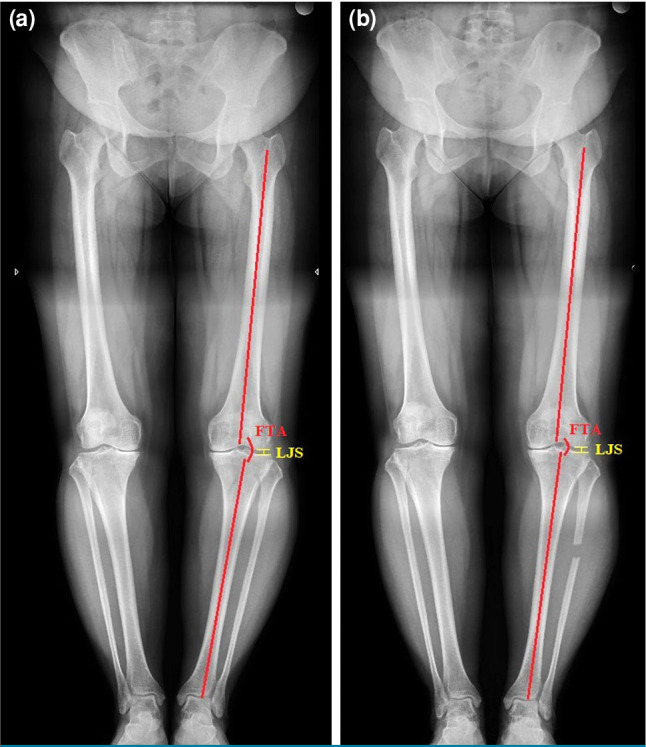

Patients and methods: Between January 2017 and January 2023, a total of 90 patients (47 males, 43 females; mean age: 50.9±5.8 years; range, 40 to 59 years) who underwent PPFR or OWHTO for early-stage medial compartment knee OA were retrospectively analyzed. The patients were divided into two groups based on the surgical technique: Group 1 (n=48) included those who underwent PPFR, while Group 2 (n=42) comprised those treated with OWHTO. Clinical outcomes were evaluated using the Visual Analog Scale (VAS) and the Western Ontario and McMaster Universities Osteoarthritis Index (WOMAC). Radiographic measurements included femorotibial angle (FTA) and lateral joint space (LJS).

Results: Both procedures demonstrated a significant improvement in function and pain. The mean postoperative FTA change was greater in the OWHTO group (7.69±1.35°) compared to the PPFR group (2.87±1.24°, p=0.001). The mean LJS changes were not statistically significant between the groups. Postoperative WOMAC and VAS scores improved in both groups, indicating no significant difference. Minor complications included transient peroneal nerve symptoms in the PPFR group, which resolved spontaneously at three months postoperatively.